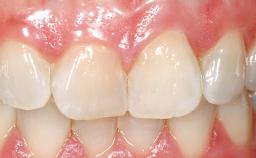

A 42-year-old female patient was referred to our clinic at the School of Dentistry of the University of São Paulo in November 2004, presenting a deficient restoration in the upper left central incisor. The clinical examination revealed no gingival retraction or any signs of gingival inflammation and, therefore, previous periodontal treatment was not considered. The patient presented a high lip line at full smile and a thin tissue biotype. This combination characterized a high-risk situation from an anatomic point of view, which required careful preoperative planning and cautious surgical execution.

Lip Line No exposure of papillae Exposure of papillae Full exposure of mucosa margin

Periodontal Phenotype Low-scalloped, thick Medium-scalloped, medium-thick High-scalloped, thin

Defining Characteristics One missing tooth to be replaced by an implant-borne crown

Mesio-Distal Space Symmetry +/- 1 mm of contra-lateral tooth